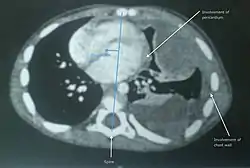

![]() ساركومة الأنسجة الرخوة غير المتمايزة في الرئة اليسرى للطفل الصغير. ساركومة الأنسجة الرخوة غير المتمايزة في الرئة اليسرى للطفل الصغير. | |